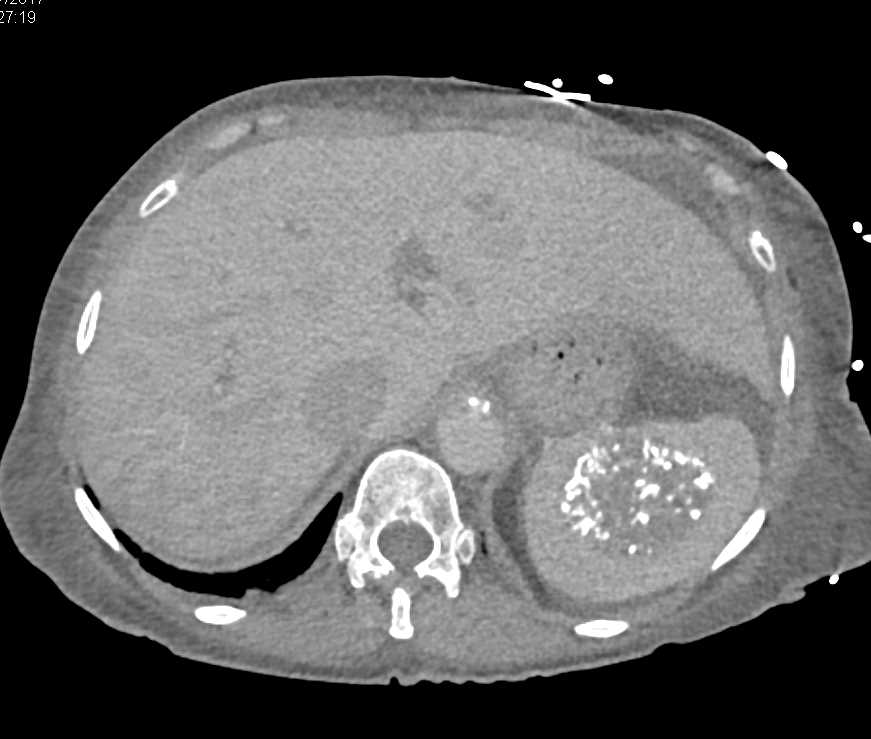

Portal Hypertension with Large Varices